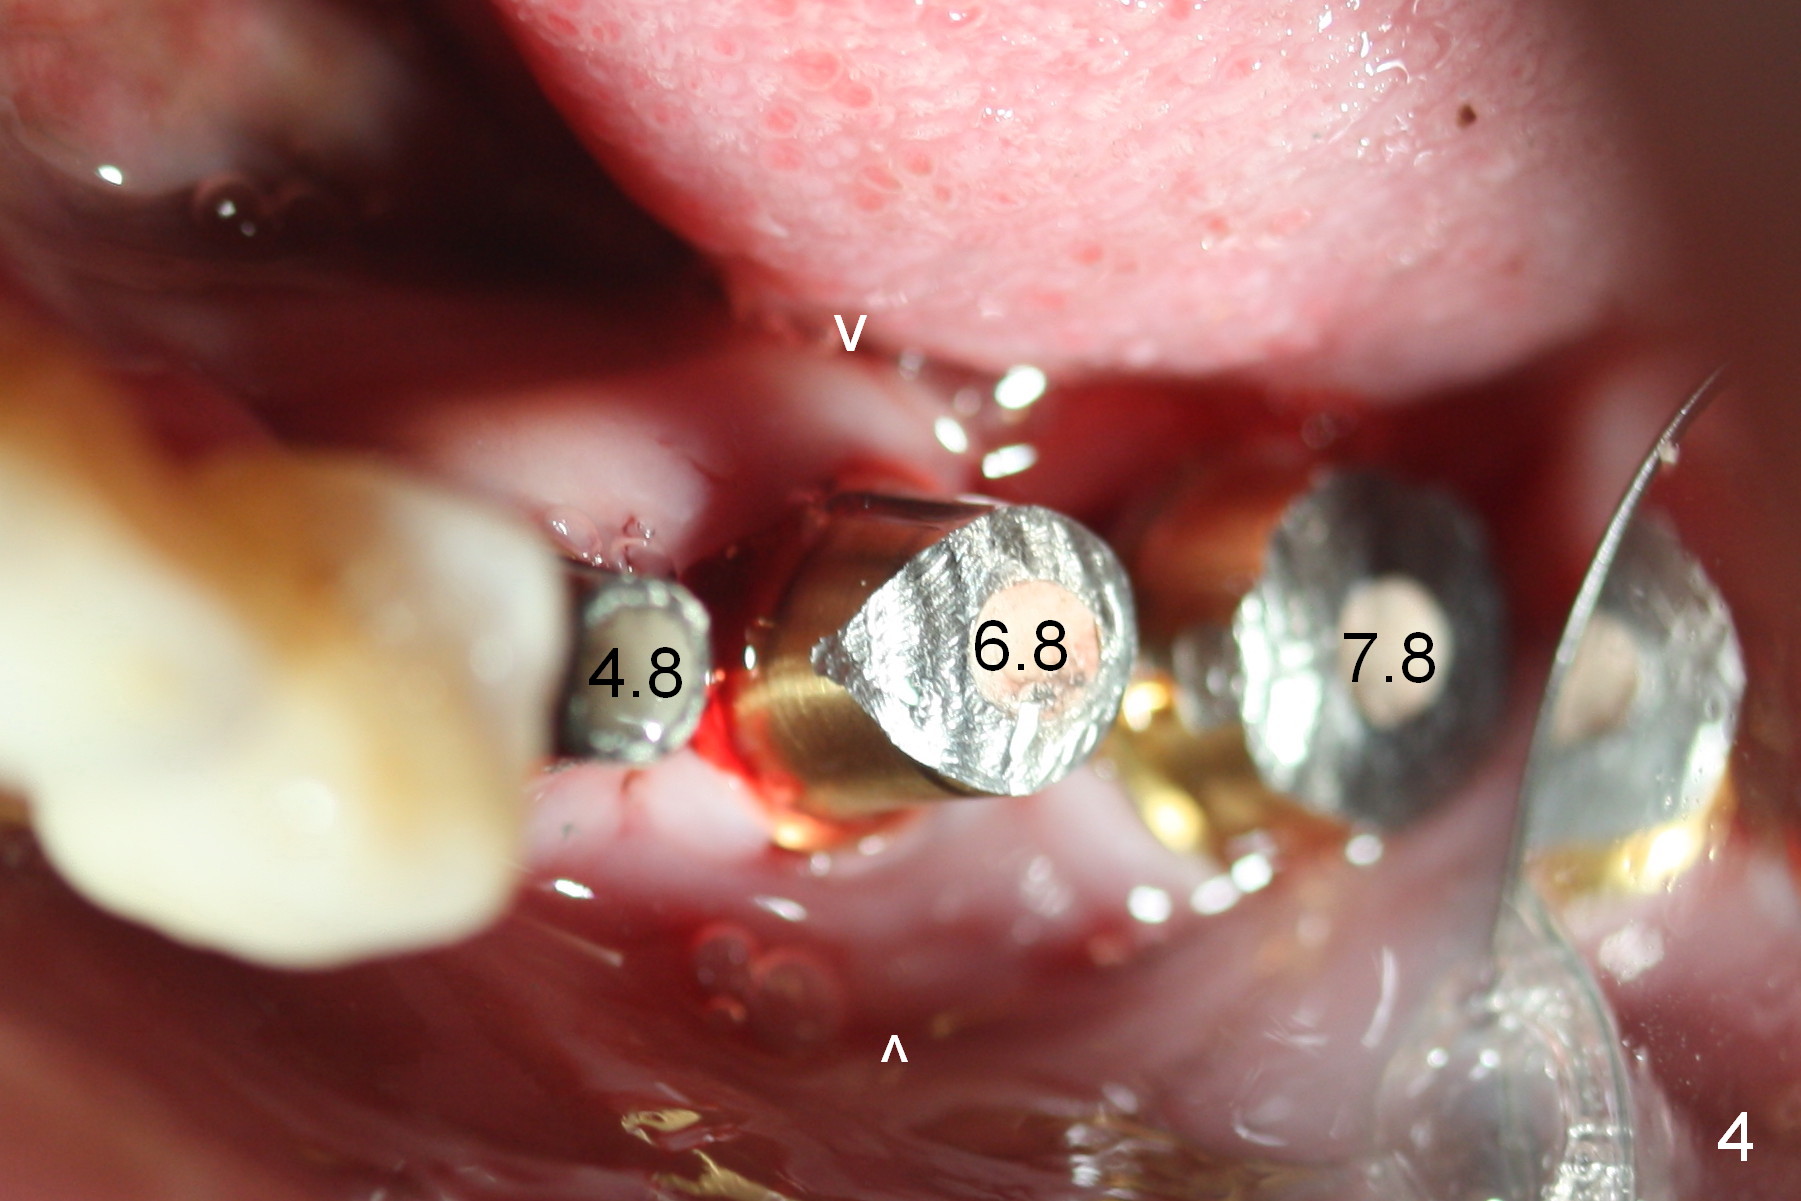

Although bone height is limited, the crest of the lower left area appears to be wide (Fig.1 arrowheads). Initial osteotomy depth is 6 mm (at #18) and 8 mm (19,20) with sufficient clearance from the Inferior Alveolar Canal (Fig.2 red dashed line). The size of the implants at the sites of #18-20 is shown in Fig.3 in millimeters. The insertion torque is around 50 Ncm. When abutments are immediately placed (the diameter and size shown in mm in Fig.4,5) and autogenous bone is packed around the implants/abutments, the ridge looks particularly wide (arrowheads). A splinted immediate provisional is fabricated.

The patient returns for final restoration 4 months postop. He is a smoker with poor oral hygiene. The provisional is fractured at #19 (distobuccal). There is a gap mesial to #18 abutment. It appears that there is mild bone loss, particularly mesial to the implant at #18 (Fig.5,6 *). The implants should have been placed deeper to prevent periimplantitis. When the abutment at #18 (7.8x4(3) mm) is removed, there is food debris mesial, although the gingiva remains healthy. A smaller abutment with shorter cuff is placed (6.8x4(2) mm) before impression.